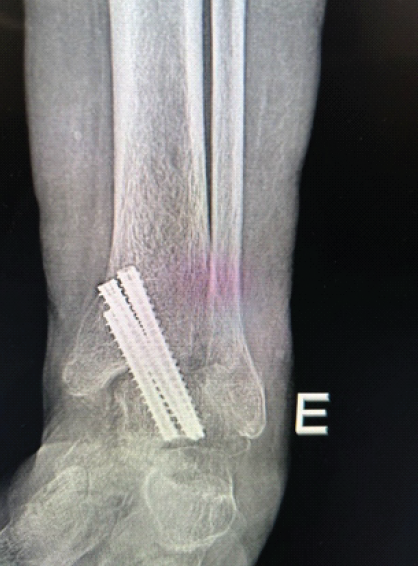

A 68-year-old male patient, a former smoker, obese with a body mass index of 41, and hypertensive, was diagnosed with severe acute respiratory syndrome coronavirus 2 infection in 2022, requiring prolonged hospitalization (45 days) in an intensive care unit. As an orthopedic sequela, he developed a rigid equinus deformity of the left ankle, resulting in impaired ambulation without the assistance of an ankle-foot orthosis with a heel wedge and a cane. After specialized orthopedic evaluation, surgical treatment consisting of Achilles tendon tenotomy and arthroscopic ankle arthrodesis was indicated. With the patient in the supine position under spinal anesthesia and sedation, the surgical procedure was performed in two stages: First, a posterior approach to the Achilles tendon approximately 4 cm proximal to its insertion was made, and, under direct visualization, the tenotomy was performed. Next, through standard anterolateral and anteromedial arthroscopic portals, anterior synovectomy and removal of the articular cartilage were carried out. Fixation for the ankle arthrodesis was achieved using three 6.5 mm diameter double-compression conical screws, all inserted medially (Fig. 1).

Figure 1: Fixation for the ankle arthrodesis.